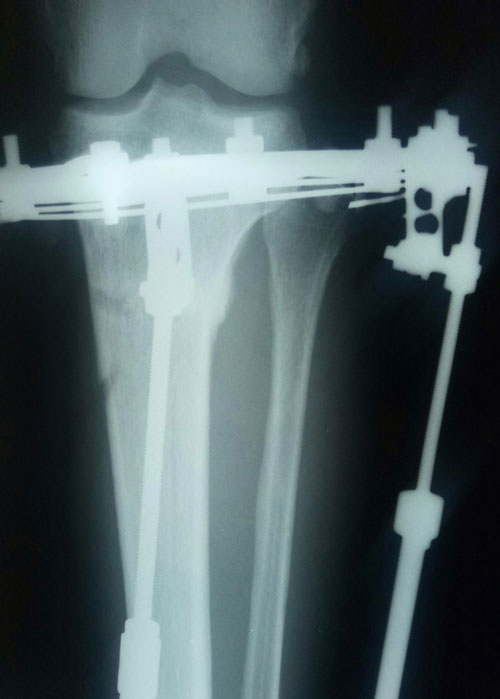

Дата операции- 30.11.2018г.

Дата снятия аппаратов - 12.03.2019г.

Срок сращения - 100 дней.